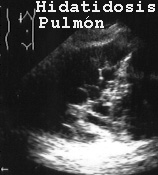

La imagen de un quiste hidatidico pulmonar se ve en la Fig 54